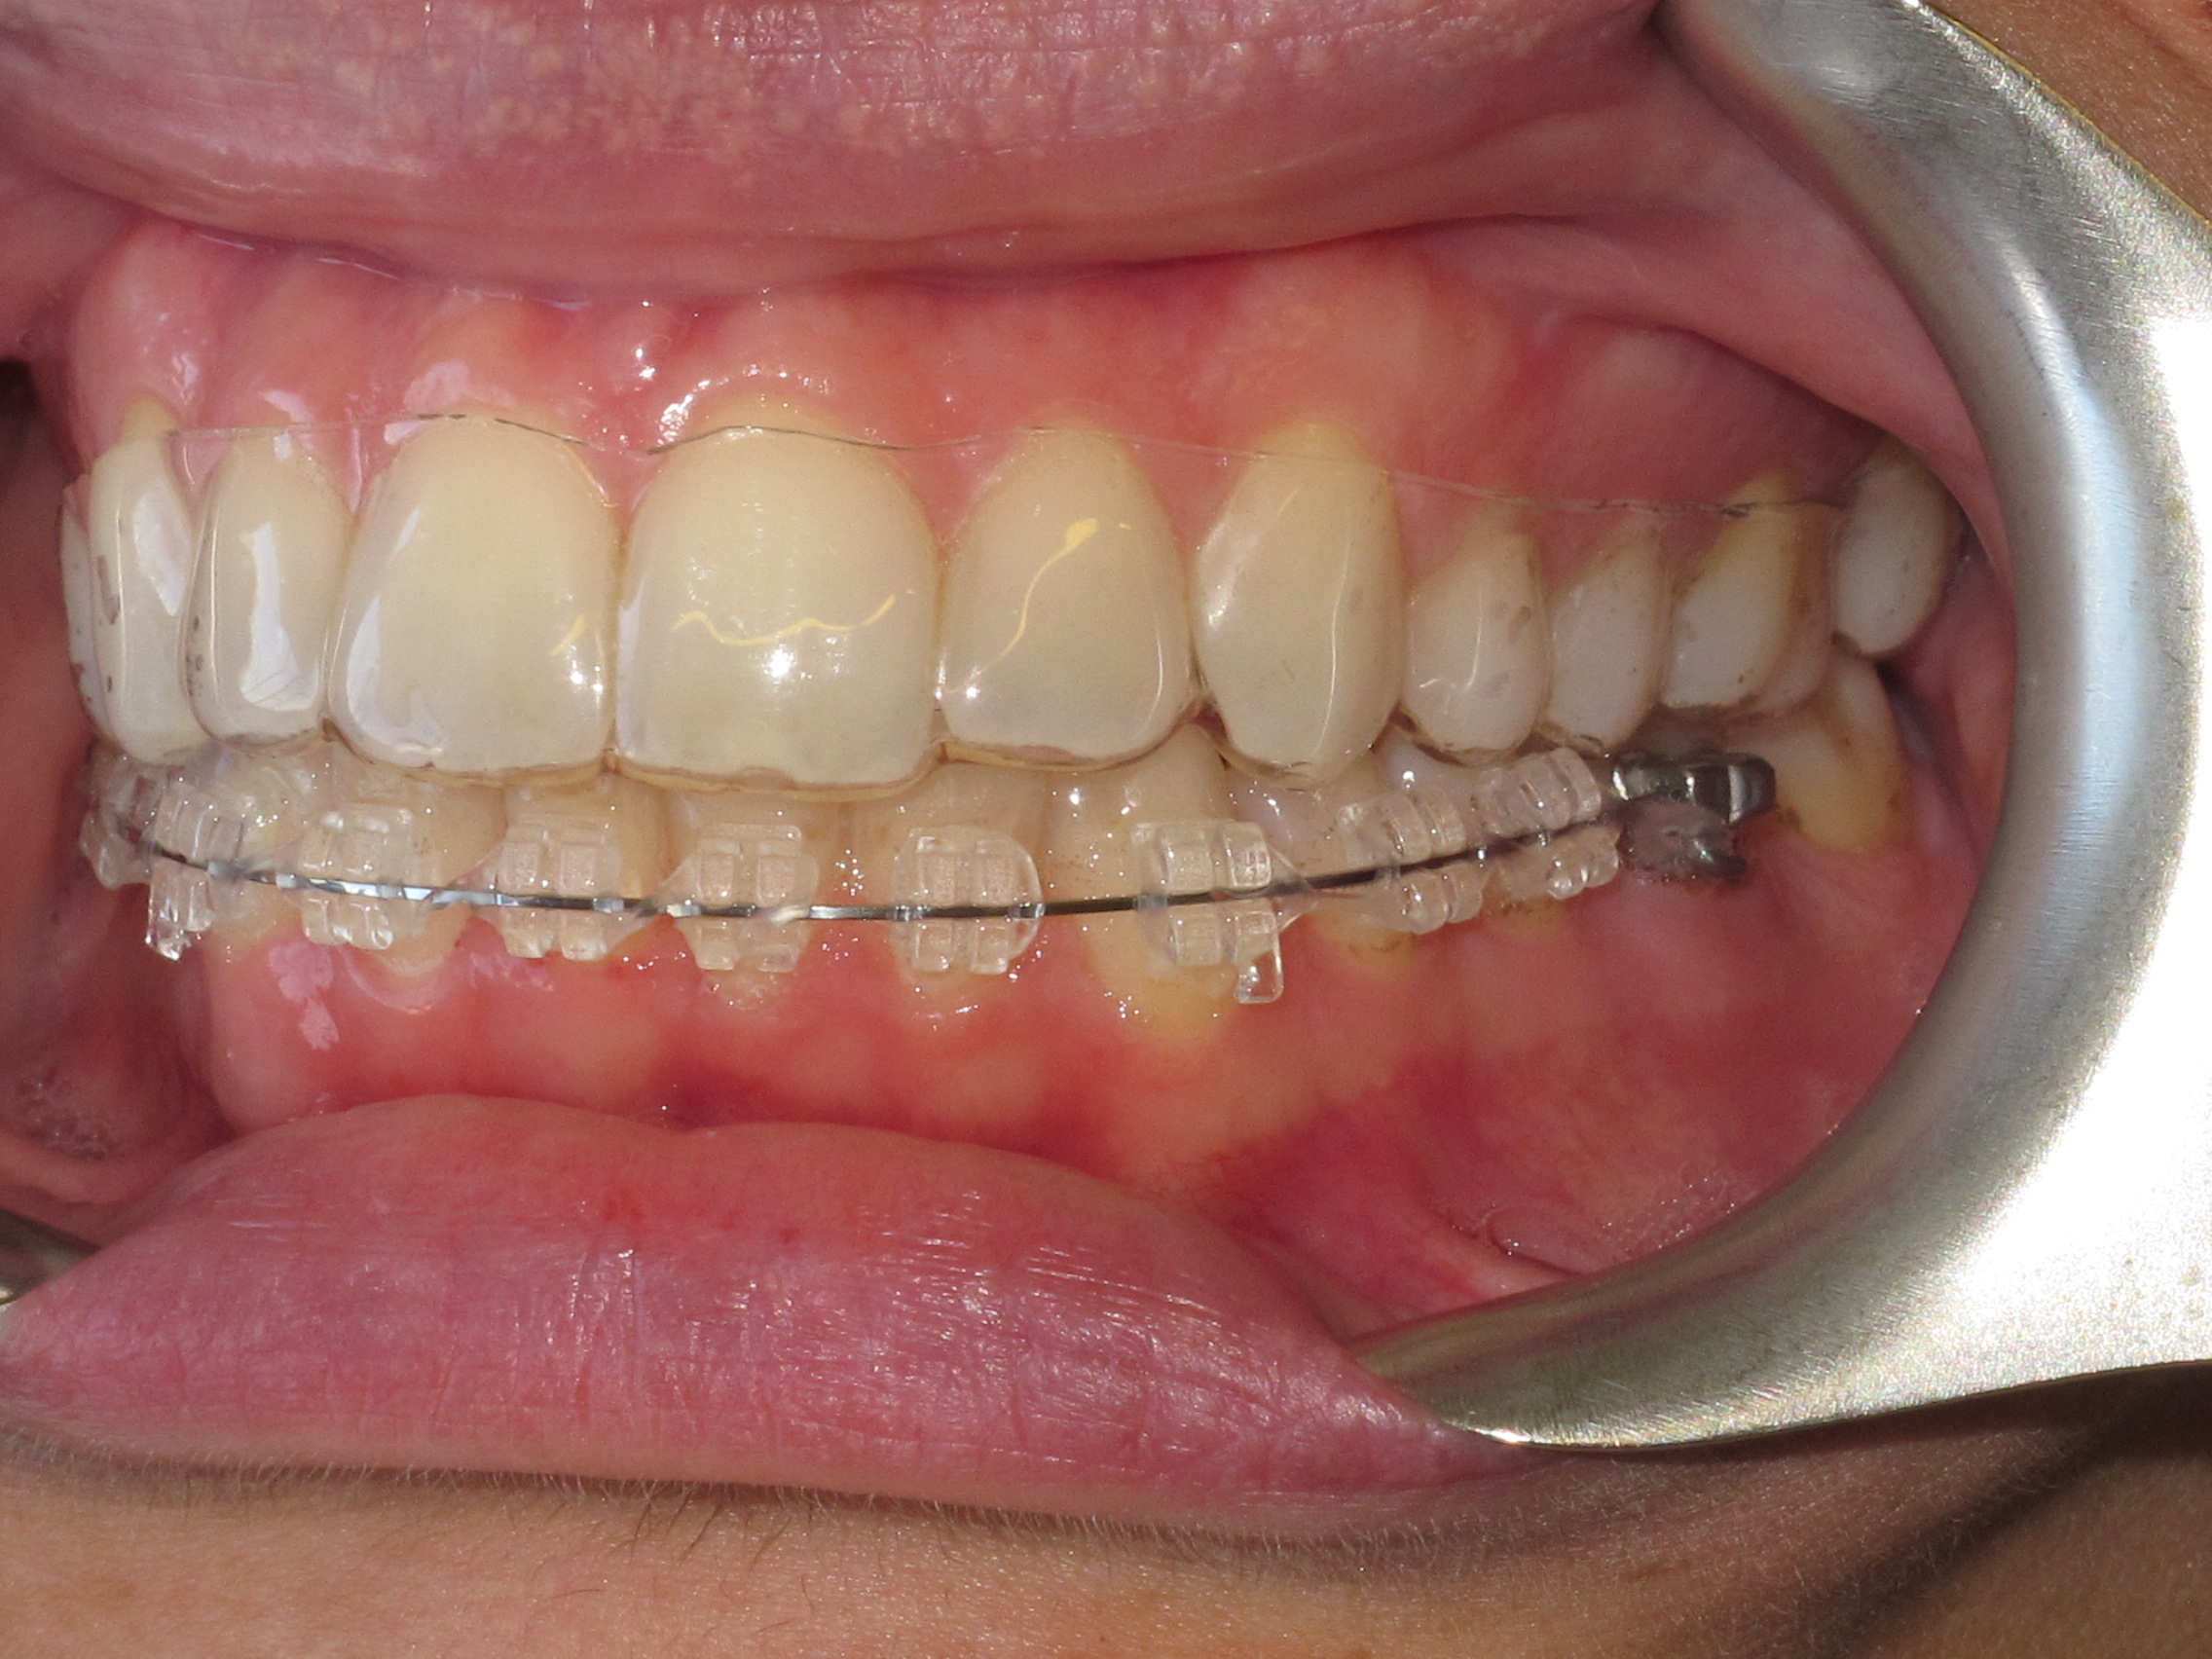

Ακίνητοι Μηχανισμοί - Ορθοδοντικός Δρ. Ζαρμπή

Πρόκειται για μηχανισμούς που συγκολλούνται στα δόντια και δε μπορούν να αφαιρεθούν από τον ασθενή. Απευθύνονται σε μετακινήσεις ακριβείας μεμονωμένων δοντιών κατά μήκος του άνω ή κάτω οδοντικού τόξου, ή οδοντικών ομάδων μεταξύ τους.

Αποτελούνται από πολλά διαφορετικά τμήματα που λειτουργούν ως ένα σύστημα το οποίο με περιοδικές ρυθμίσεις επιτυγχάνει τις επιθυμητές οδοντικές μετακινήσεις. Ακολουθεί ανάλυση των τμημάτων των ακίνητων μηχανισμών:

Τα κεραμικά άγκιστρα - Ορθοδοντικός Δρ. Ζαρμπή

Τα κεραμικά άγκιστρα ενδείκνυνται σε ασθενείς με αυξημένες αισθητικές ανάγκες. Το χρώμα τους δεν αλλοιώνεται εφόσον τηρούνται οι κανόνες στοματικής υγιεινής εκτός εάν ο ασθενής κάνει υπερβολική χρήση έγχρωμων υγρών (καφές, τσάι, coca-cola) οπότε είναι δυνατόν το χρώμα να αλλάξει ελαφρώς.

Αυτά είναι πιο εύθραυστα από τα μεταλλικά η δε δαπάνη της θεραπείας είναι αυξημένη.